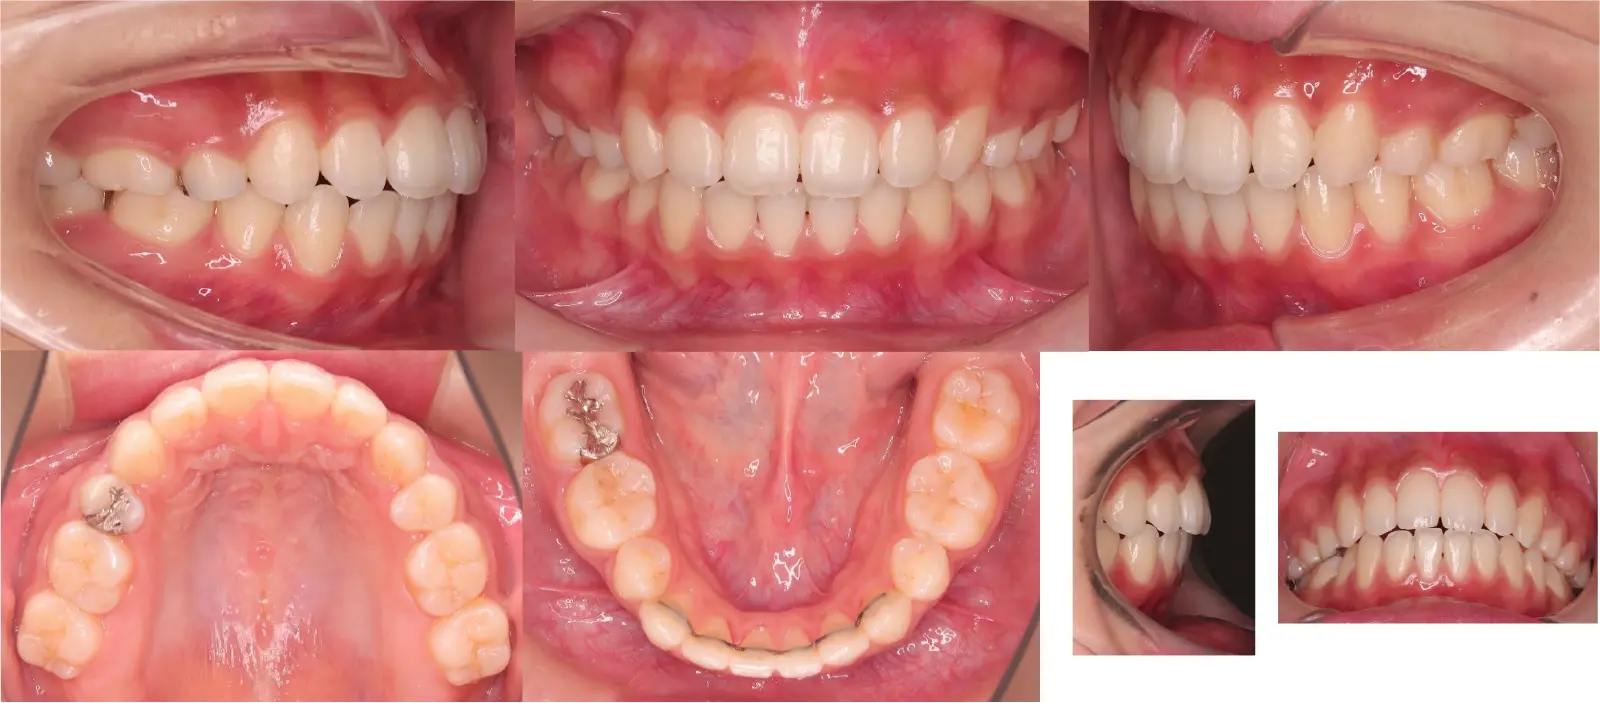

アングルⅡ級 開咬を伴う上顎前突症

- 主訴

前歯がかみ合わない

- 年齢

10代

- 治療期間

2年1ヶ月

- 治療回数

24回

- 治療に用いた主な装置

カスタムメイド型マルチブラケットタイプのデジタル矯正装置(インシグニア)

i-station(口蓋型アンカースクリュー)

- 治療費

650,000円(税別)、調整料5,000円(税別)

※伊那分院にて治療

- 抜歯部位

上顎第一小臼歯2本

下顎第二小臼歯2本